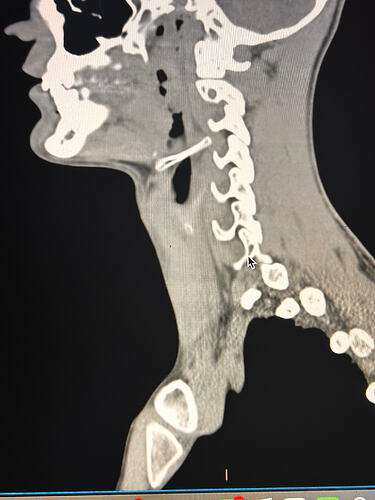

Here are some of my 2-d scans, thanks. The top one is my right greater horn and the bottom is the left

Thank you for the additional images. After reading @Jules observations, I went back over the first 4 images you sent & realized I’d miss some significant things. I’ve annotated more images for you below:

This one shows your right hyoid greater horn from behind.

I totally missed that I could see your whole hyoid bone from the front in this image. Jules is right, your greater horns are very thick from top to bottom. You can also see that your left greater horn is pretty straight, but the right one has an upward curve to it. I’m not sure what the calcification is below your hyoid but it’s most likely thyroid since the thyroid sits just below the hyoid in the neck.

In this image, you can see the differences in the shapes of your hyoid’s greater horns. The right one is more curved but the left one is thicker in width medial to lateral. In this image from the front it looks like both greater horns may be contacting your cervical spine in certain head positions, but again, that may an illusion created by the angle of the image.

In the final two images you sent, the right greater horn is very close to your cervical spine so there’s a good chance it’s causing you some problems as well as possible carotid artery irritation or compression in different head positions. The image of the left one doesn’t show as much of the greater horn so I can’t tell how close to the spine it is. Can you back the left image out a bit so it looks more like the right one?

I was trying to get an image of the whole greater horn on the left but I could only get small glimpses of it as I went through the slides. Maybe because of its shape. As far as pain on the right that is where I usually notice issues, especially the lump I feel whenever I swallow, although the left can also get very tight and painful at times.